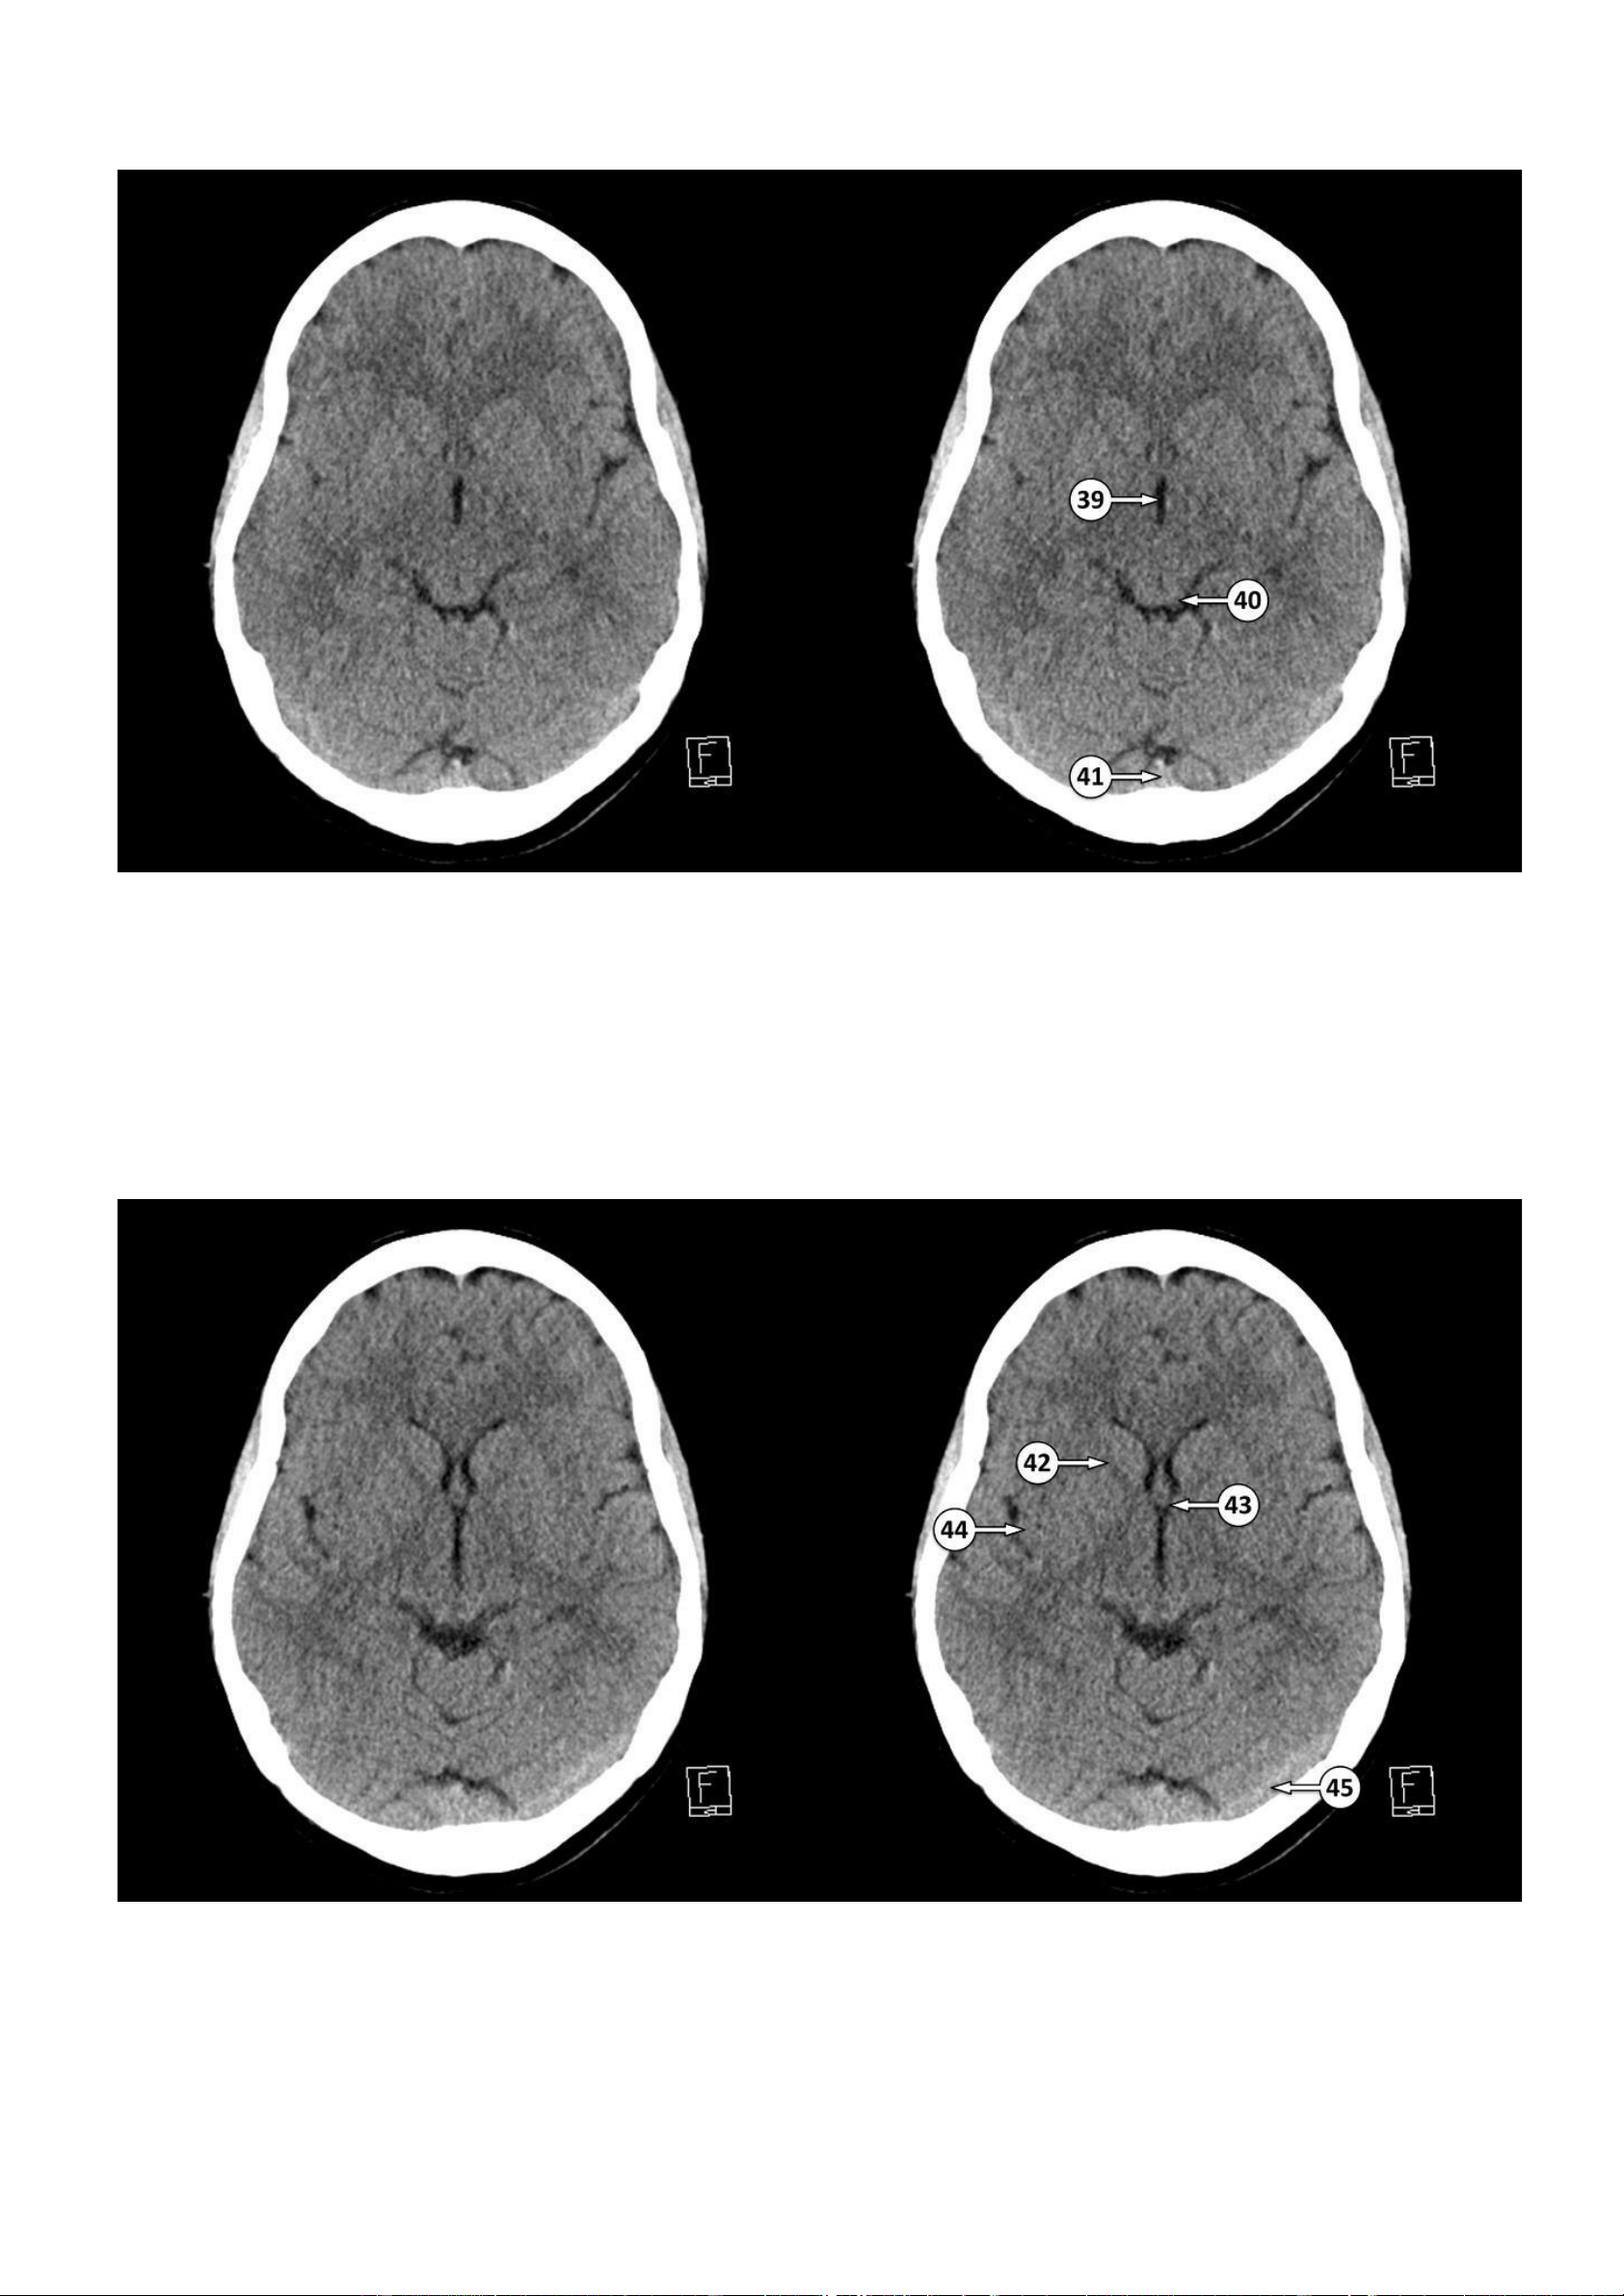

Thảo Thảo & Bé Nghìn Dặm ▪ Số 39: Não thất III

▪ Số 40: Củ não sinh tư dưới

▪ Số 41: Hợp lưu các xoang tĩnh mạch màng cứng

▪ Số 42: Cánh tay trước của bao trong

43: Lỗ gian não thất (lỗ Monro) 44: Vỏ não thuỳ đảo lOMoAR cPSD| 22014077

Thảo Thảo & Bé Nghìn Dặm 45: Xoang ngang lOMoAR cPSD| 22014077